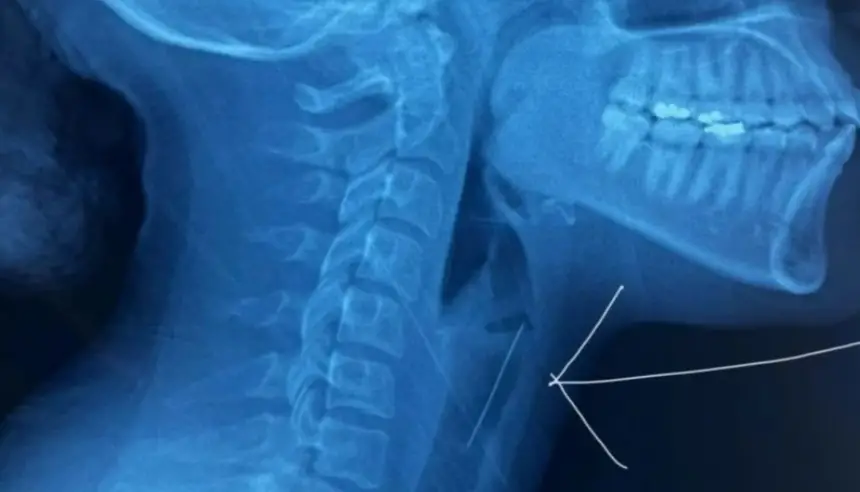

ووفقاً لمصادر طبية، فقد وصلت الشابة إلى المستشفى وهي في حالة حرجة، بعدما استقر الدبوس المعدني في منطقة حساسة من الحنجرة، مما شكل تهديداً مباشراً على مجرى التنفس. وبعد سلسلة من الفحوصات الطبية الدقيقة، تبين أن التدخل السريع هو الخيار الوحيد لتجنب كارثة صحية خطيرة.

باحترافية عالية، نجح الطاقم الطبي في استخراج الدبوس باستخدام منظار حنجري متطور مزود بكاميرا دقيقة، مكنهم من إزالة الجسم الغريب دون التسبب بأي أضرار جانبية للقصبة الهوائية أو الأنسجة المحيطة، وسط مراقبة طبية مستمرة لضمان استقرار وضعها الصحي.